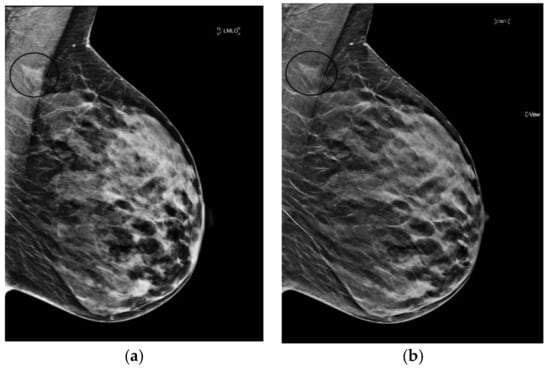

6.3. Architectural Distortion

The reconstruction algorithm’s enhancement of line structures can also emphasize the appearance of architectural distortions (AD). Taken together with the ability of tomosynthesis to clear away superimposed tissue, s2D+DBT can permit confident identification of subtle cancers presenting as AD. (Figure 3).

Figure 3.

Architectural Distortion (circled in black) detected on screening mammogram with synthesized mammography and confirmed on tomosynthesis images (slices shown here), permitting confident Breast Imaging Reporting and Data System (BIRADS) 0 assessment. After diagnostic work-up and biopsy, pathology confirmed well-differentiated invasive ductal carcinoma, ER/PR+, Her2-, with grade 1 ductal carcinoma in situ. (a) s2D CC (b) DBT slice CC (c) s2D mediolateral oblique (d) DBT slice mediolateral oblique.

Giess et al. showed architectural distortions were significantly more conspicuous on synthesized mammography compared to FFDM (p < 0.001) [39]. Indeed, Mariscotti et al. found poor concordance in classification of AD between s2D and 2D FFDM (κ = 0.36), with six malignant ADs missed on 2D FFDM [33]. As s2D is derived from the DBT dataset, it may retain more information on tissue structure from the multiple projection images compared to 2D FFDM, emphasizing mammographic findings like AD.

Freer et al. reported no significant change in recall rates for AD with synthesized mammography [31]. This may reflect that AD characterization is best defined by tomosynthesis images, rather than by 2D or synthesized 2D.

It is important to note that normal ligaments may also be enhanced and present as possible distortions. As with calcifications, confirmation in both planes and with tomosynthesis can avoid false positive recalls. Careful diagnostic work-up and wariness of distortions that “spot away” remains prudent, given the high probability of malignancy of ADs. Additional studies could explore whether use of s2D increases detection of benign radial scars/complex sclerosing lesions, which may also present as AD.